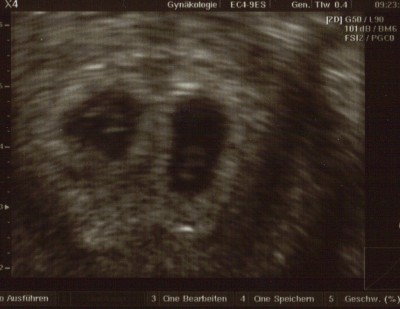

aber ich konnte es nicht sooo lange ohne ein Bild aushalten und war heute bei meinem FA hab ihm das erklärt und er meinte gar kein Thema bin heute auch 6+0 ja was soll ich sagen ich habe Zwillinge und beide Herzchen pochen, nur der eine ist einen Tag vorraus wie der ander aber er meinte das wäre bei Zwillingen normal, mein nächster termin ist in 10 Tagen habe 4 Bildchen mit bekommen ich bin echt platt vor Freude natürlich und meine Angst wächst bei 2en natürlich noch mehr das nichts passiert ;(

Kannst ja mal ein Bild reinstellen von Deinen beiden Krümeln ... büüüttteeee

Mach dir echt keine Gedanken bis Dienstag ist nicht mehr lange und das Wochenende liegt ja auch dazwischen da wird sich dann was tun bei meinem 1. US in der Klinik war ich 4+3 und heute bin ich 6+0 bei mir wurde es ab dem Tf berechnet und laut dem Us stimmt es auch überein eines ist sogar einen Tag vorraus ich versuche es mal dran zu hängen aber man erkennt nicht richtig gut wa sist unscharf wenn es nicht klappt gib mir deine E mail Adresse okay???